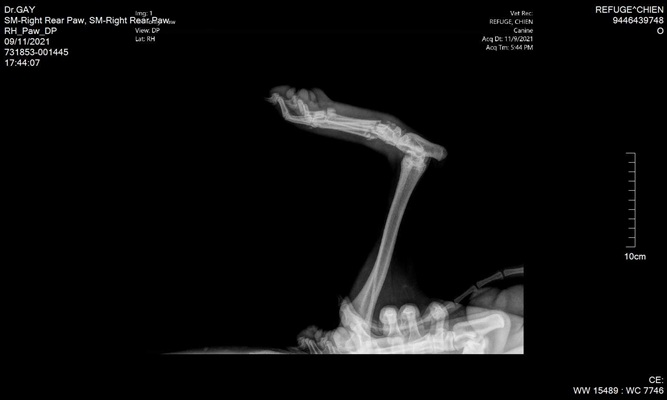

Mittelfußfraktur - OP am 22.11.2021

BRADLEY hat die OP gut überstanden und hat am 03. Dezember 2021 die Klinik verlassen können und ist bis zum Transport am 11. Dezember 2021 auf einer französischen Pflegestelle.